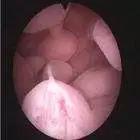

我们常见的是通过 TVS也就是经阴道超声检查,还可以通过三维超声以及注水超声,宫腔镜检查。尤其宫腔镜检查,可直视下观察子宫内膜息肉,且定位精准,同时摘除息肉或进行活检,有很大的优势,已成为诊断和治疗子宫内膜息肉的“金标准”,是目前普遍推荐的手术方式。